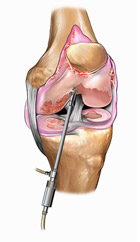

Con l’avvento negli anni ’80 dell’artroscopia (procedura chirurgica mininvasiva che, attraverso l’utilizzo di minitelecamere a fibre ottiche e di strumentari dedicati, permette l’accesso a una articolazione senza aprirla), la chirurgia soprattutto del ginocchio e della spalla si sono radicalmente evolute. Dopo qualche decennio di applicazione ed evoluzione tecnologica, attualmente quasi tutte le articolazioni più importanti possono essere aggredite artroscopicamente. Ciò ha reso possibile il trattamento di innumerevoli lesioni con traumi chirurgici molto ridotti favorendo i processi di guarigione e il recupero funzionale.

Nei casi in cui i sintomi dolorosi persistono o nei casi previsti, le rotture meniscali sono trattate anch’esse artroscopicamente con ottimi risultati. Le lesioni più periferiche (nella cosiddetta “zona rossa”) hanno qualche chances di guarire e per questo motivo possono essere suturate (nei pazienti giovani). Le rotture più comuni, tuttavia, avvengono nella zona più interna, la meno vascolarizzata (“zona bianca”); non avendo possibilità di cicatrizzarsi, la parte del menisco rotta viene semplicemente asportata.

- shaving cartilagineo o condroabrasione: è una procedura artroscopica che prevede la pulizia della cartilagine rovinata per renderla più liscia e per asportare eventuali corpi mobili che potrebbero creare blocchi articolari;

- microfratture: si tratta di microperforazioni tramite strumenti artroscopici che, eseguite nelle zone con difetti cartilaginei, provocano il sanguinamento dell’osso sottostante; durante questo processo, vengono liberate cellule staminali che innescano un processo di formazione di un tessuto di riparazione fibro-cartilagineo.